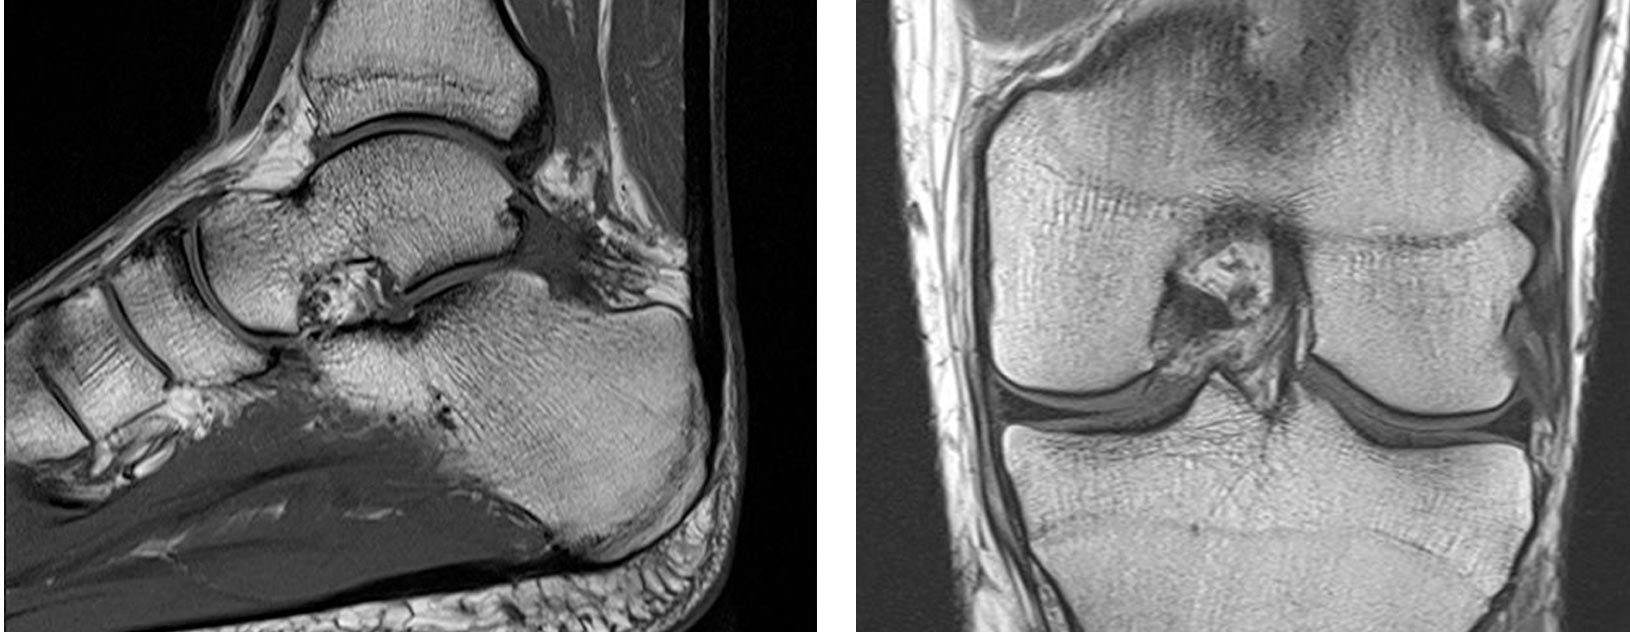

Magnetic Resonance Imaging is a non-invasive technique which uses a combination of magnetism and radio waves to produce a detailed series of images of the body part concerned. It does not involve radiation and is an extremely safe form of imaging. Depending on the body part being imaged the patient may have to partly of fully enter the magnet but it will not come into contact with the patient at any point.

MRI Arthrography involves MRI imaging of a large joint such as shoulder, hip, wrist and elbow following injection of “dye” into the joint. The radiologist performs this injection into the joint using a needle under ultrasound or fluoroscopic guidance.